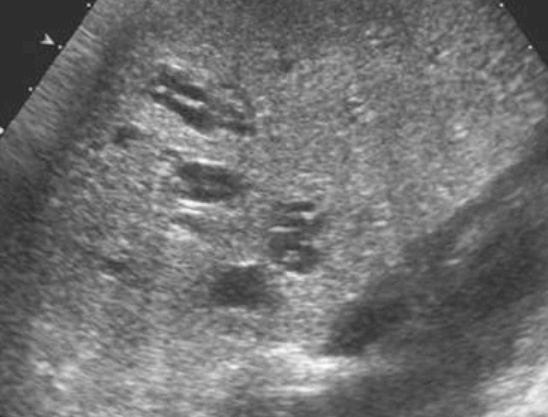

US finding

- 전반적으로 에코가 거칠게 보이는 간경변의 초음파소견과 비슷하여 주의가 필요함.

- 크기가 비슷한 고에코 또는 저에코 병변들이 보인다.

- 다중반사에 의한 comet-tail artifact를 보인다.

담도과오종 (Biliary harmatoma) 담관 주변 낭종 (Peribiliary cyst)